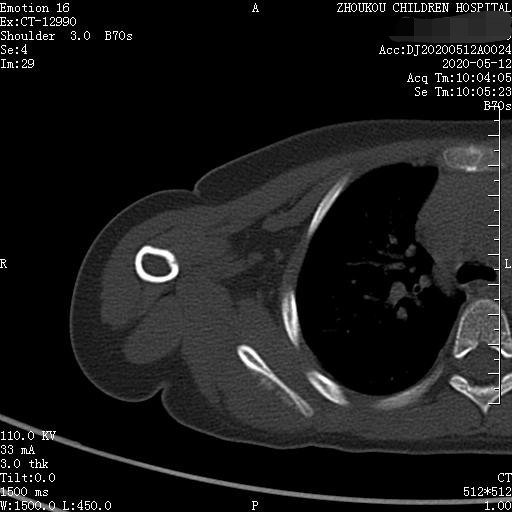

3岁女童以突发右侧肩胛部肿物来院检查,病人无发热、感冒症状,拍右肩关节正位片示:右侧肩关节肩胛岗上缘骨质密度欠均匀,建议CT进一步检查。

通过CT平扫发现:右侧肩胛骨骨质密度不均,骨质内可见“虫食样”低密度影,骨质边缘可见多发放射状骨针,呈“日光射线征”。周围软组织明显肿胀,肌间隙模糊。CT检查意见:考虑:右肩胛骨占位,骨肉瘤可能,不除外其它恶性肿瘤病变,请结合临床及相关检查关注复查。 影像鉴别诊断:骨肉瘤是指起源于骨间叶组织,遗留形成骨细胞直接形成骨样组织为特征的恶性肿瘤,是比较常见的骨恶性肿瘤,好发于十到二十岁青少年,骨肉瘤常见于管状骨,股骨远端胫骨近端最多见,表现为疼痛局部肿胀运动障碍,实验室检查都有碱性磷酸酶升高。

二、根据骨质破坏和肿瘤骨的多少,骨肉瘤可以分为三型,液化型以肿瘤新生骨为主,溶骨型是以骨质破坏为主,混合型新生骨的形成和骨质破坏并存,x线表现是不规则的骨质破坏伴浸润,可见日光样和放射状骨膜反应,骨膜新生骨在破坏可形成考特曼三角,骨内可见云状、絮状、针状、放射状肿瘤骨伴软组织肿块而形成。